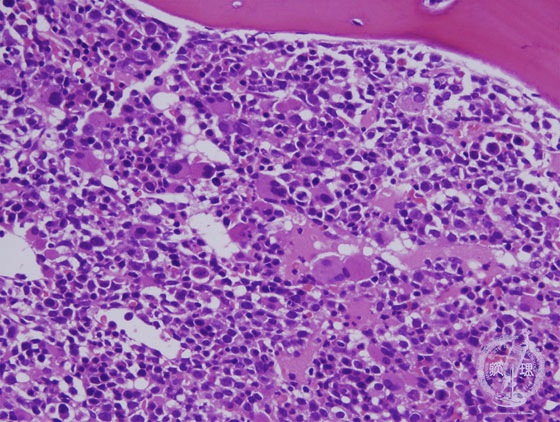

Microscopic image (H&E intermediate power view): The marrow of MDS is hypercellular by excessive blasts with disordered differentiation in varying degrees. This picture represents as gMDS, an increased risk of progression to AMLh by WHO classification. It is also categorized as RAEBt according to FAB classification. Dysplastic differentiation is found in many lineages other than myeloblastes. There is a marked increase in the number of megakaryocytes with irregular shape of nuclei in this picture.